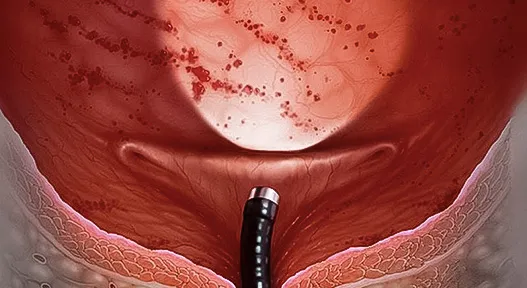

Prostat

Laparoskopik ve endoskopik yöntemlerle konforlu ve hızlı iyileşme imkânı sağlıyoruz.